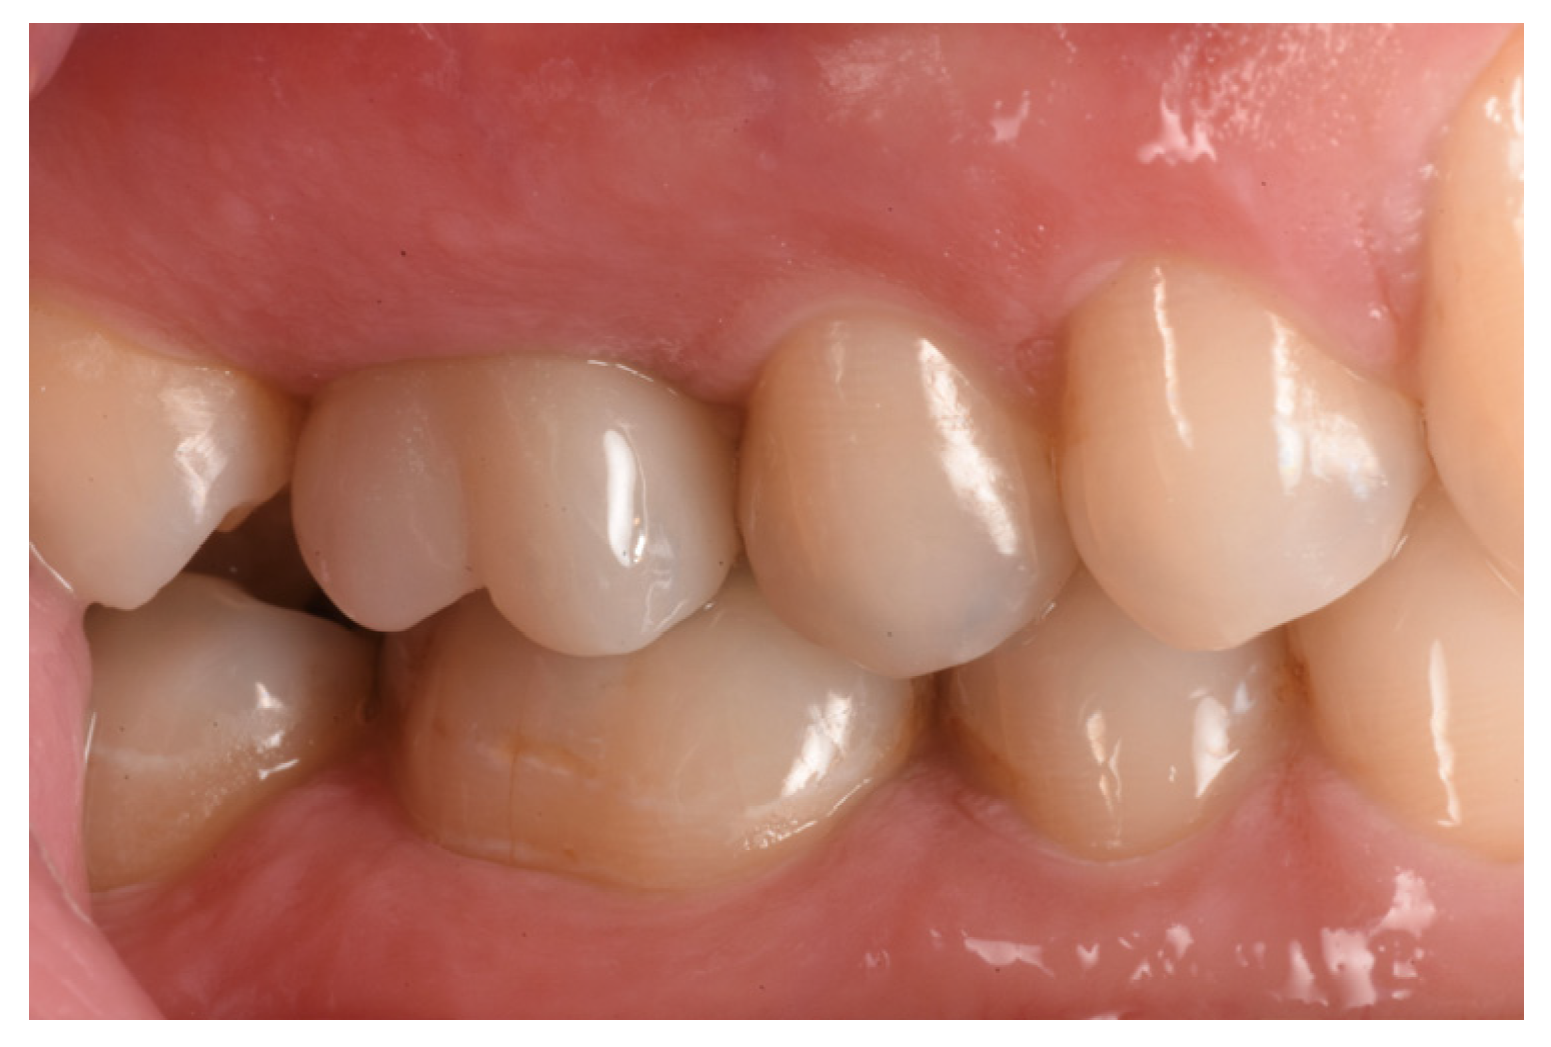

2.6. Case Presentation. Nano-HA Applied to Socket Preservation Procedures

3. Results